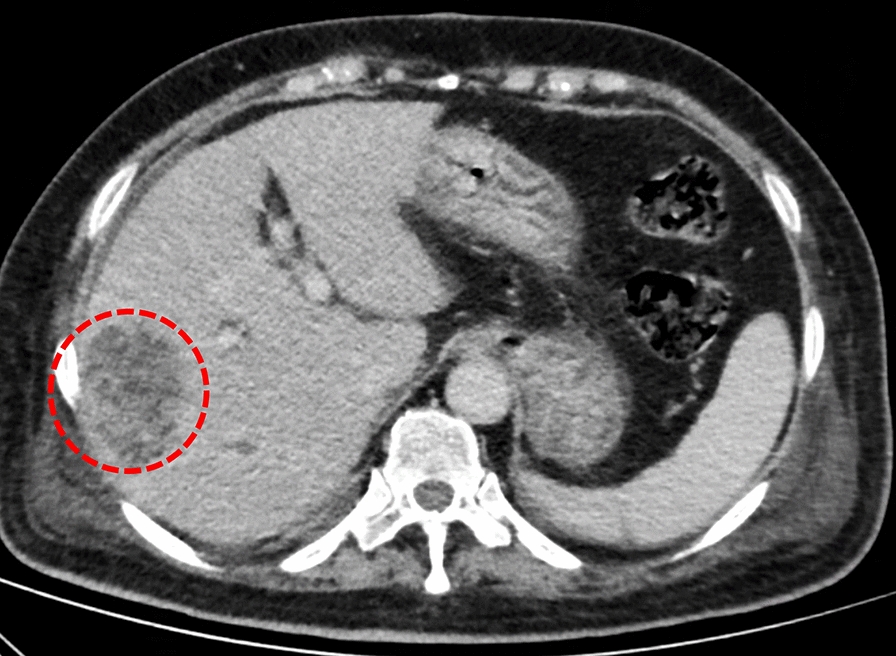

Case report: A 75-year-old Han Chinese female patient who presented to the emergency department primarily for fever accompanied by chills was diagnosed with pyogenic liver abscess complicated with pulmonary infection, involving multiple pus emboli in the branches of the right hepatic vein. The patient accepted intravenous imipenem and cilastatin sodium for anti-infection, and subcutaneous insulin to control hyperglycemia. Percutaneous liver puncture and drainage was performed under ultrasound guidance. During the treatment the patient presented with headache, weakness in both lower limbs and lower back pain. Brain magnetic resonance imaging showed intracranial infection and lumbar magnetic resonance imaging showed infection of the vertebral body, intervertebral disc, and soft tissue. The patient had a liver abscess positive for Klebsiella pneumoniae together with infection of other organs, thus she was eventually diagnosed with invasive Klebsiella pneumoniae liver abscess syndrome. The antibiotics were adjusted according to the site of infection and drug sensitivity test. The patient recovered after percutaneous liver puncture and drainage under ultrasound guidance and anti-infection treatment for 3 months. Reexamination of abdominal computed tomography, chest computed tomography, brain magnetic resonance imaging and lumbar magnetic resonance imaging suggested that the infectious lesions had disappeared.